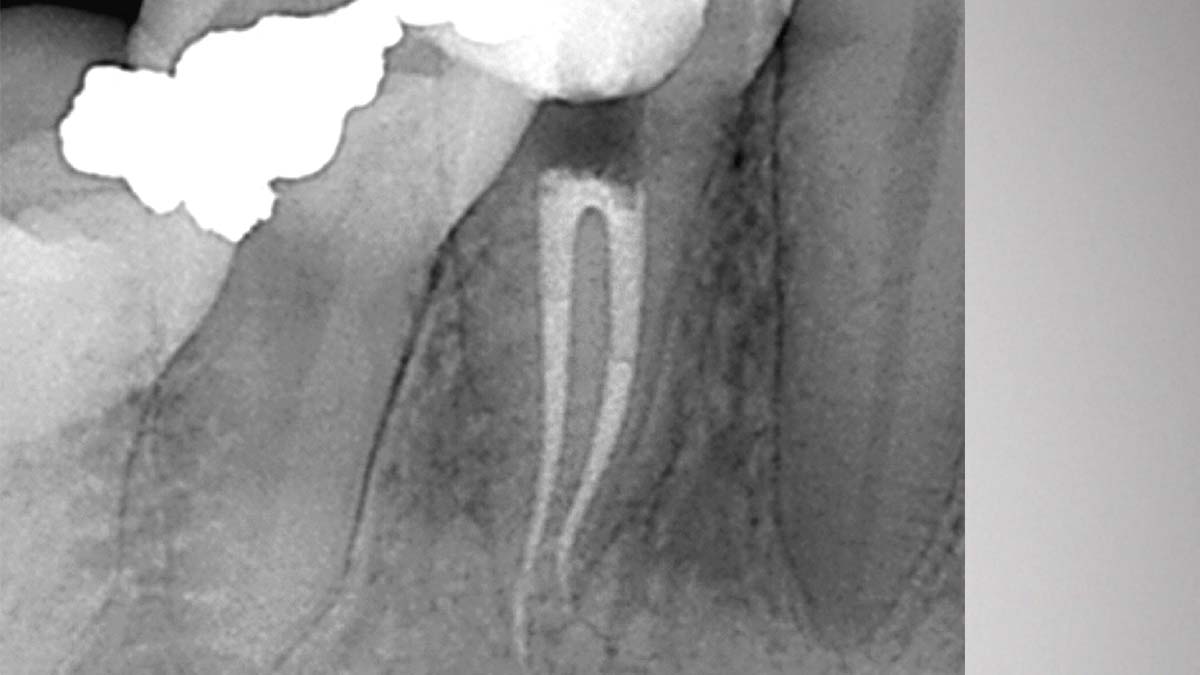

À gauche : l’utilisation de différentes formulations de gutta-percha dans un même cas peut entraîner différents degrés d’opacité.

Avec l’aimable autorisation du Dr Phillip Bell, Mooresville, NC